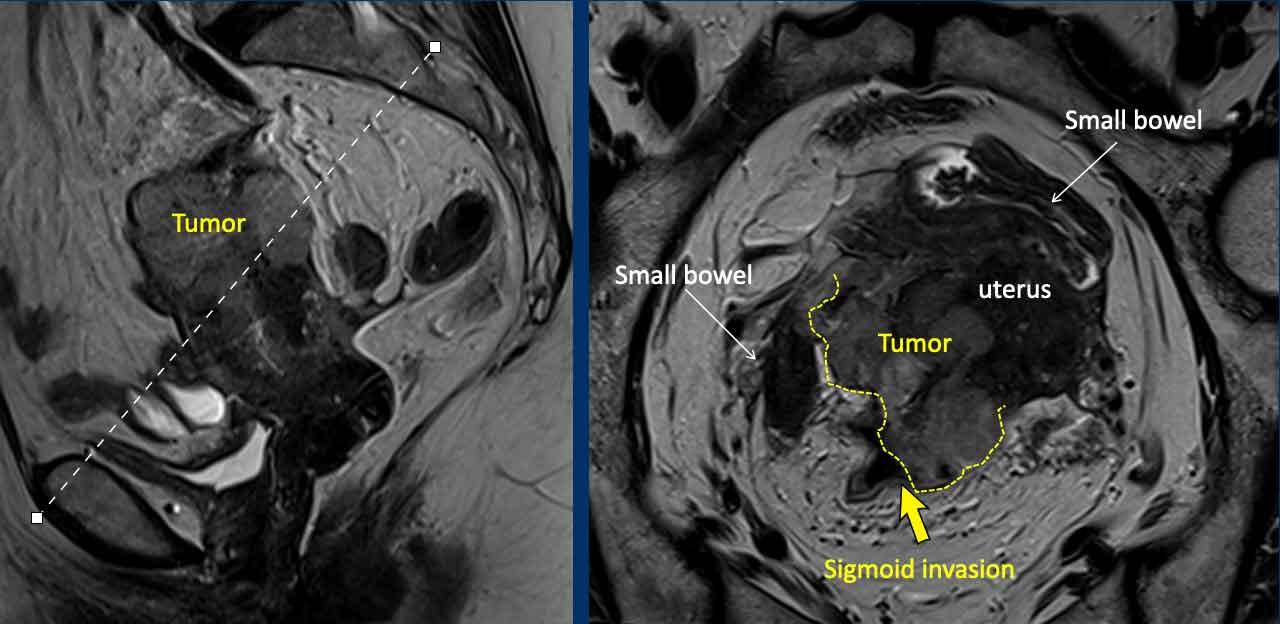

Xâm lấn ngoài tử cung (bao gồm xâm lấn bàng quang và trực tràng)

Khi phát hiện được, đây là bệnh giai đoạn tiến xa cần được ghi rõ trong báo cáo vì sẽ ảnh hưởng đến phương pháp phẫu thuật.

Hình ảnh

Đây là một ví dụ hiếm gặp về ung thư nội mạc tử cung tiến xa tại chỗ, phát triển vượt qua thanh mạc tử cung ở phía sau và xâm lấn đại tràng sigma (mũi tên).